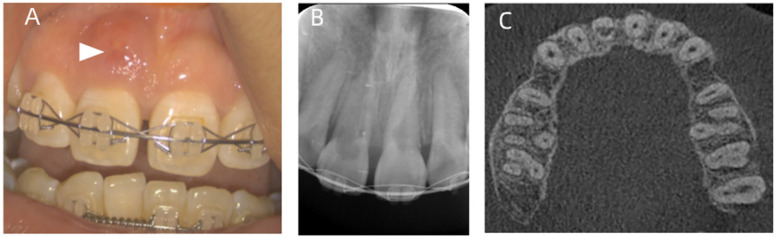

牙根吸收是正畸治疗后的主要并发症之一。这是一种涉及缺血性坏死的炎症过程。因此,它被称为正畸诱导炎症根吸收(OIIRR)。本报告的目的是提出一个病例研究的患者在她的20谁经历了内根吸收在两个上颌中门牙的正畸治疗的结果。将三氧化二矿聚集体(mta)应用于根吸收损伤以促进再矿化。经过3年的随访,临床和影像学检查显示未发现与吸收性病变相关的透光度,无任何病理症状。

Root resorption is one of the leading complications that follows orthodontic treatment. It's an inflammatory process involving ischemic necrosis. Therefore, it is called orthodontically induced inflammatory root resorption (OIIRR). The purpose of this report is to present a case study of a patient in her 20s who experienced internal root resorption on two maxillary central incisors as a result of orthodontic treatment. Mineral trioxide aggregates (MTAs) were applied to the root resorption lesion to promote remineralization. A clinical and radiographic examination revealed that no radiolucency related to the resorptive lesion was found without any pathological symptoms after a 3-year follow-up.